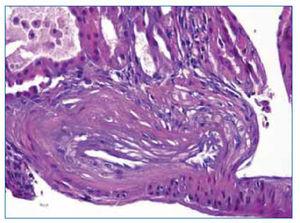

Ante la situación metábólica, se coloca catéter venoso central y se inicia hemodiálisis, quedando el paciente hospitalizado. Durante el ingreso presentó un pico febril, demostrándose en los hemocultivos crecimiento de Staphylococcus epidermidis. Asimismo, se cultivó el exudado de la úlcera del primer dedo del pie con crecimiento igualmente de Staphylococcus epidermidis (con igual perfil de sensibilidad antibiótica que el de los hemocultivos). Con antibioterapia específica la evolución fue favorable, desapareciendo la fiebre, aunque persiste la lesión del pie. Al consultar con Traumatología, esta confirma la presencia de osteomielitis del primer dedo, manteniendo el tratamiento antibiótico de forma prolongada. Desde el punto de vista renal, persiste oligoanuria con necesidad de diálisis. Ante la no recuperación de la función renal, a los 12 días del ingreso se realiza biopsia renal percutánea, encontrando en la muestra: 10 glomérulos, 1 con esclerosis global (10 %) y el resto presentaban de forma global y difusa una proliferación endocapilar con patrón lobular, asociada a un componente agudo exudativo formado principalmente por neutrófilos y eosinófilos; en las membranas se observaban áreas de fragmentación, de engrosamiento y muy escasas imágenes de duplicación (figura 1); había engrosamiento fibroso periglomerular de la cápsula de Bowman y componente extracapilar epitelial focal (1 glomérulo que ocupaba < 25 % del volumen glomerular); no se veían imágenes de necrosis glomerular; en el intersticio había parches de infiltrado inflamatorio mixto agudo (neutrófilos y eosinófilos) y crónico, junto a áreas de fibrosis y de atrofia tubular leve; imágenes de tubulitis aguda, escasos cilindros hialinos, cristales y hematíes intratubulares; había una arteriola con hialinosis intimal y una arteria con fibrosis laminal miointimal (figura 2); la IF presentaba depósitos granulares mesangiales intensos (3+) y moderados (2+) lineales capilares para C´3 de distribución global y difusa (figura 3); depósitos focales y segmentarios mesangiales granulares de intensidad leve (1+) para C1q e IgG; negatividad para fibrinógeno, IgA, IgM. El cuadro histológico es compatible con una glomerulonefritis proliferativa aguda difusa posinfecciosa con componente extracapilar mínimo, que se consideró relacionada etiopatogénicamente con la osteomielitis por Staphylococcus epidermidis, dada la coincidencia temporal de ambos cuadros.

Figura 1.HxE. Glomérulo con patrón lobular, congestivo, con exudado agudo en el espacio endocapilar, con abundantes polimorfosnucleares, con algunos eosinófilos. Engrosamiento difuso mesangial sin dobles contornos.